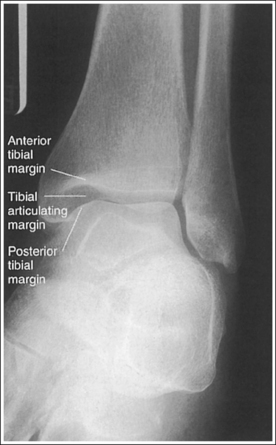

• Evaluating the openness of the tibiotalar joint. On an AP ankle projection, determine whether an open joint was obtained and whether the tibia is demonstrated without foreshortening by evaluating the anterior and posterior margins of the distal tibia. On an AP ankle projection with accurate positioning, the anterior margin is demonstrated approximately 0.125 inch (3 mm) proximally to the posterior margin (see Figure 6-48). If the proximal lower leg was elevated or the central ray was centered proximal to the tibiotalar joint, the anterior tibial margin is projected distally, resulting in a narrowed or obscured tibiotalar joint space (see Image 34). If the distal lower leg was elevated or the central ray was centered distal to the tibiotalar joint, the anterior tibial margin is projected more proximally to the posterior margin than on an AP ankle projection, expanding the tibiotalar joint space and demonstrating the tibial articulating surface (see Image 35).

The tibiotalar joint space is open, and the tibia is demonstrated without foreshortening.

• The tibiotalar joint space is open and the tibia is demonstrated without foreshortening when the patient's lower leg was positioned parallel with the IR and the central ray was centered at the level of the tibiotalar joint (see Figure 6-52).

• Evaluating the openness of the tibiotalar joint. On an AP oblique ankle projection, you can determine whether the positioning and central ray alignment goals have been met by evaluating the anterior and posterior margins of the distal tibia. On an AP oblique ankle projection with accurate positioning, the anterior margin should be visualized approximately 0.125 inch (3 mm) proximal to the posterior margin. If the proximal lower leg was elevated or the central ray was centered proximal to the tibiotalar joint, the anterior tibial margin is projected distally, resulting in a narrowed or obscured tibiotalar joint. If the patient's distal lower leg was elevated or the central ray was centered distal to the tibiotalar joint, the anterior tibial margin is projected too far proximal to the posterior margin, expanding the tibiotalar joint space and demonstrating the tibial articulating surface (see Images 39 and 40).